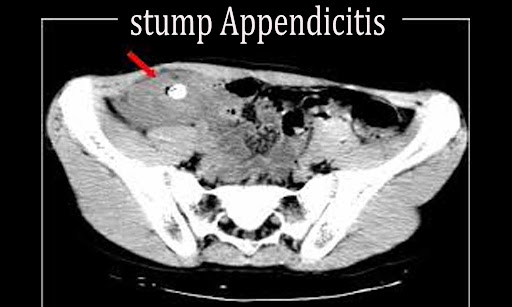

Stump appendicitis is a very rare entity. Stump appendicitis is a delayed complication of appendectomy. Where inflammation occurs in the remaining appendicular stump.

Stump appendicitis is a very rare entity that should not be a sudden increase in the incidence if laparoscopic appendectomy is performed properly, and its incidence may be minimized with. Stump appendicitis is a rare entity that occurs as a result of. Where inflammation occurs in the remaining appendicular stump.

Stump appendicitis is unlikely to occur immediately after the operation. This leads to delays in diagnosis and treatment. Patients present with symptoms similar to an initial presentation for appendicitis.

Consequently it is rarely entertained as a diagnosis in a patient who has previously undergone an appendectomy, which may lead. Stump appendicitis is defined as a rare complication following appendectomy caused by inflammation of the residual portion of the appendix left behind. Stump appendicitis is an uncommon entity;

Diagnosis is often delayed as history of appendectomy often precludes focused workup for an appendiceal source of infection. National center for biotechnology information It may occur from 2 months to 50 years following either laproscopic or open.